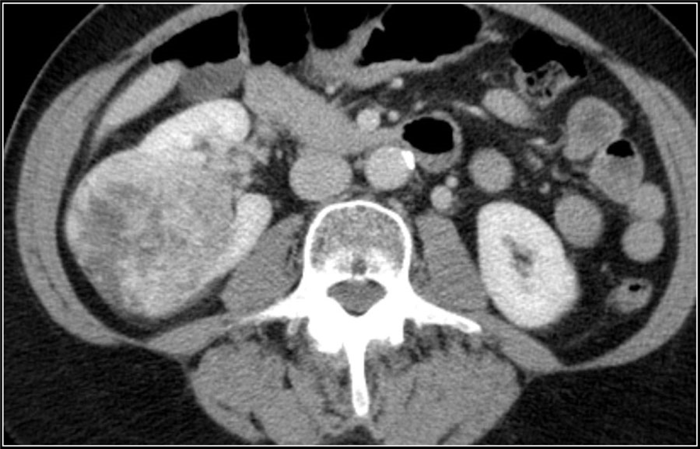

(Слева) КТ с контрастированием, аксиальная проекция: выявлена увеличенная правая почка с множественными скоплениями жидкости неправильной формы, не накапливающими контраст. Данные признаки характерны для многоочаговых абсцессов.

(Справа) КТ с контрастированием, аксиальная проекция: выявлены многокамерные абсцессы почки с ободковым контрастированием и абсцессы околопочечного пространства.